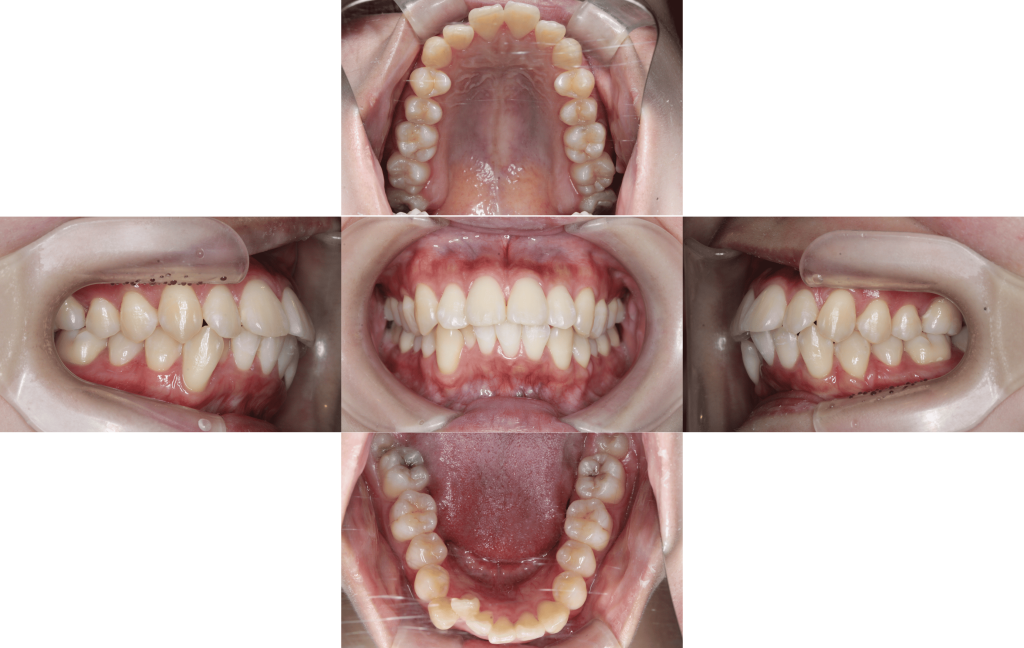

Before

初診